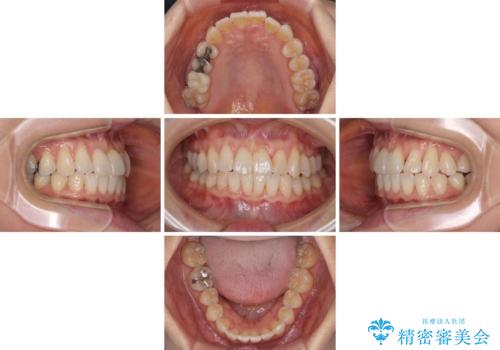

前歯のクロスバイト インビザライン矯正で改善

- むし歯治療を契機に、長年気にしていた前歯のクロスバイトの改善を希望された患者様です。

汚れが溜まりやすく、歯ぎしりがうまくできないため、インビザラインを用いて矯正治療を行うこととしました。

インビザラインによる前歯のクロスバイトの改善は、治療期間中に前歯でしか咬めない時期が続いたり、歯肉退縮や歯髄壊死のリスクが高まったりと、治療中にトラブルを抱えることがあります。

特に上顎側切歯(真ん中から2番目の歯)が舌側に引っ込んでいるケースは、インビザラインでは改善しきれないことがあると言われています。